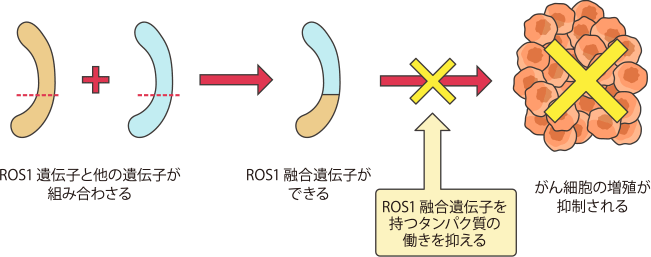

ROS1融合遺伝子は、ROS1遺伝子とさまざまな遺伝子が融合したものです。この組み合わさったROS1融合遺伝子からできるタンパク質により、がん細胞を増殖させるスイッチが入り、がん細胞が限りなく増殖してしまう働きがあることがわかってきました。

ROS1融合遺伝子は、非小細胞肺がんの約1~2%に認められます。

体内で細胞を増やしたり(増殖)、新しい機能をもった細胞に変化したりするときに働く遺伝子の1つにROS1遺伝子があります。ROS1遺伝子に何らかの異常があると、他の遺伝子と組み合わさって特殊な遺伝子ができることがあります。この特殊な遺伝子をROS1融合遺伝子といいます。

ROS1融合遺伝子はROS1遺伝子と組み合わさる遺伝子の種類によっていくつかの種類があることが確認されています。

ROS1融合遺伝子はがん細胞を増殖させる

ROS1融合遺伝子は、肺がん(非小細胞肺がん)の患者さんのうち約1〜2%の患者さんで見つかっています。また、ROS1融合遺伝子が見つかる肺がんの患者さんは、若年の方、女性、非喫煙者に多いことがわかっています。

ROS1融合遺伝子ができると、がん細胞を増殖させるスイッチが入ったままになり、がん細胞が増殖を続けます。

ROS1融合遺伝子は、EGFR遺伝子変異やALK融合遺伝子の検査と同時に検査を行うことが推奨されています。